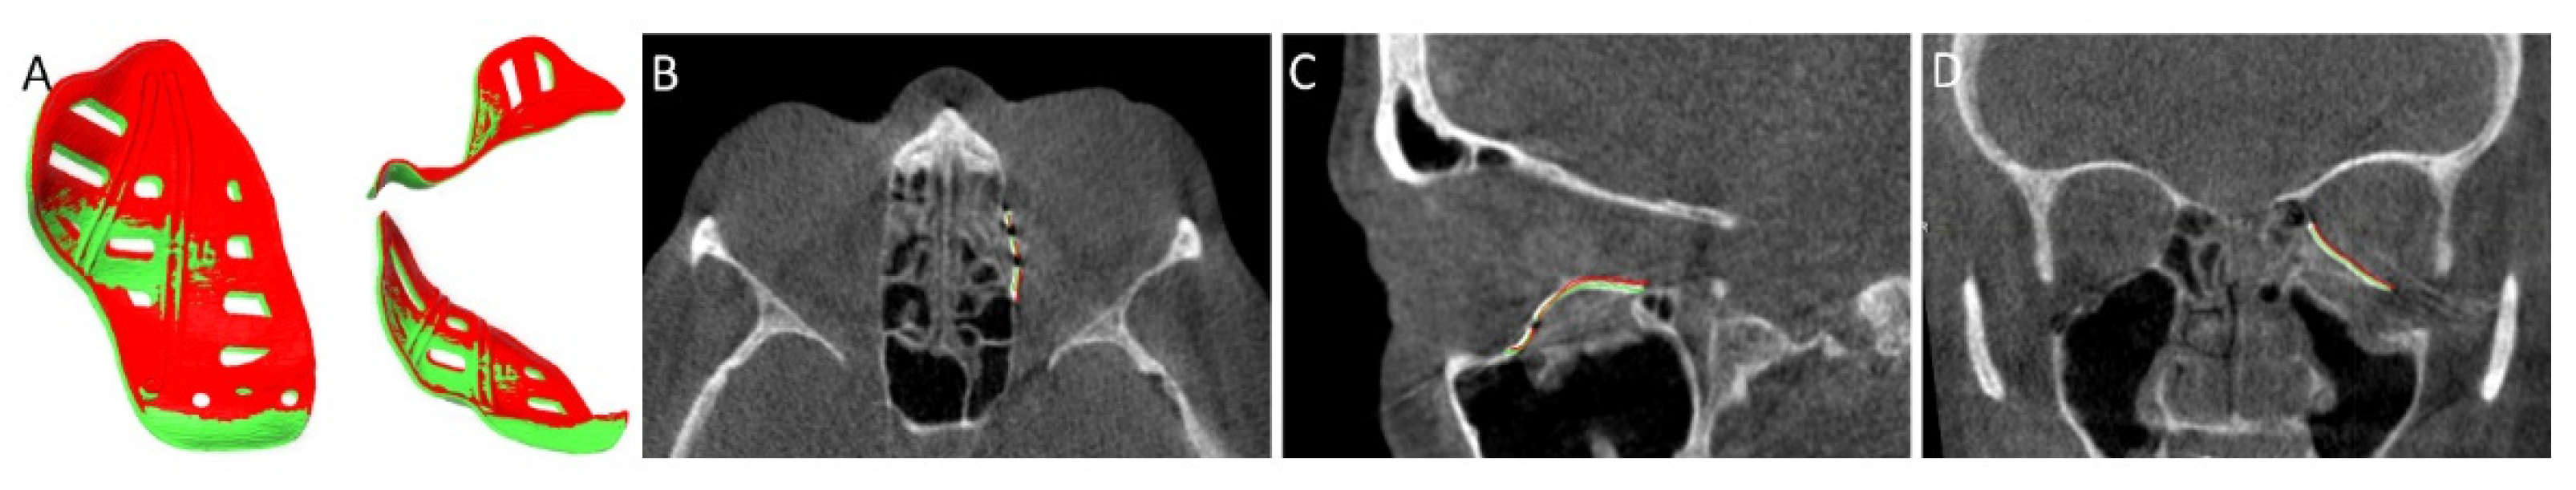

- Schreurs, R.; Dubois, L.; Becking, A.G.; Maal, T.J. Quantitative Assessment of Orbital Implant Position—A Proof of Concept. PLoS ONE 2016, 11, e0150162. [Google Scholar] [CrossRef]

| Feedback Method | Static/Dynamic |

|---|---|

| Virtual surgical planning | Static |

| Compelling fit patient-specific implant | Static |

| Fixation re-use | Static |

| Navigation | Dynamic |

| Markers and vectors | Dynamic |

| Intraoperative imaging | Static |